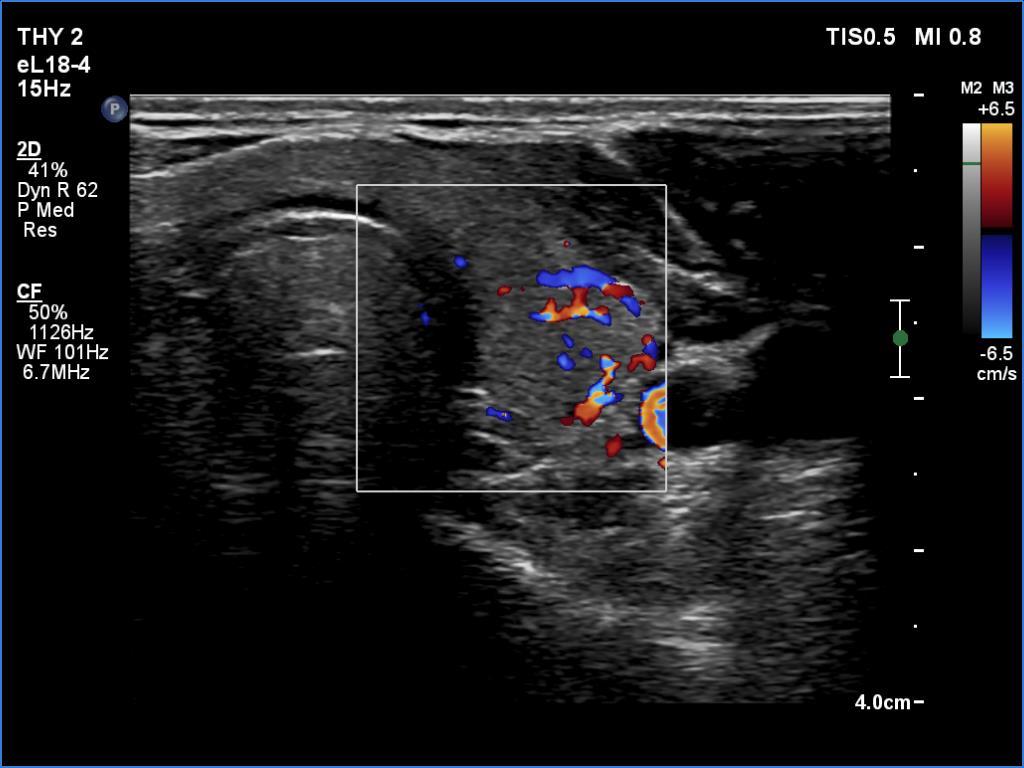

Left lobe, longitudinal scan, color Doppler mode. The vascularization is average.